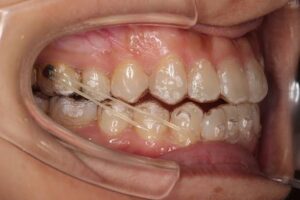

ゴムかけとは

歯列矯正治療を行う際に矯正装置(マウスピースやワイヤーなど)に

ゴムをかけることで、矯正力の補助的な力を歯に加える方法です。

ゴムかけは歯を引っ張る時や噛み合わせを合わせていく時

などに行うことが多い処置内容です。

ゴムの牽引力により、

矯正装置だけではかけられない力を歯にかけることで

適切な噛み合わせを作ることが可能になります。